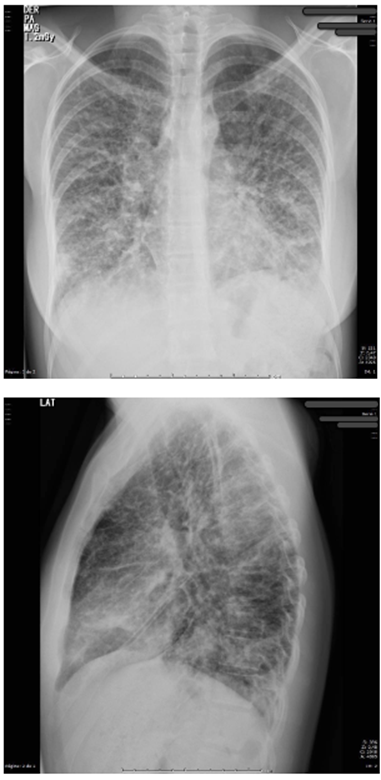

Se decidió realizar una tomografía de abdomen (figura 3) que mostró engrosamiento concéntrico de las paredes del colon sigmoide de 7 mm de espesor, de aspecto inespecífico, de probable etiología inflamatoria, asociado a coprostasis en el colon ascendente y transverso, sin observarse adenomegalias, y endoscopia de vías digestivas altas, cuyo único hallazgo fue gastritis crónica. En la radiografía de tórax de control (figura 4) se aprecian cambios dados por opacidades reticulares bilaterales en 4 cuadrantes y aumento del proceso reticular previo, por lo que se hace necesario la toma de biopsia pulmonar por parte de cirugía de tórax.